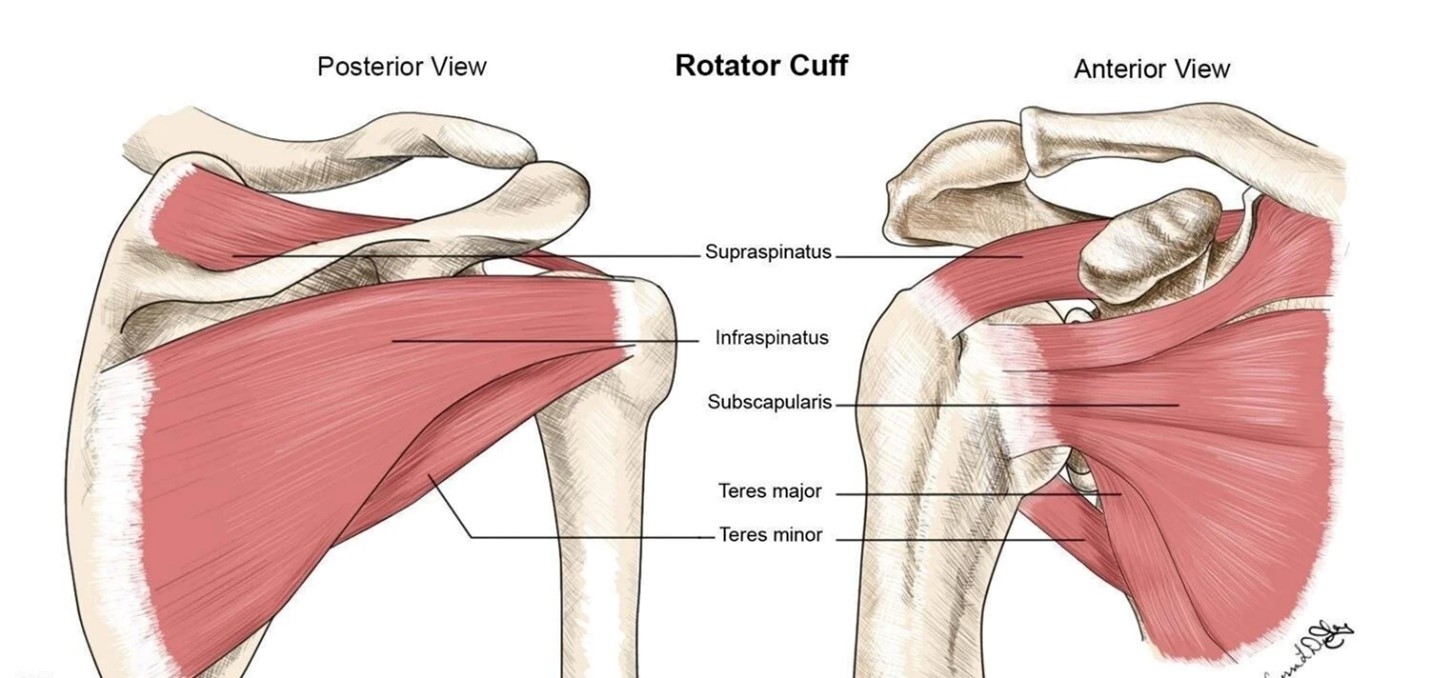

什麼是肩袖肌群?

肩袖肌群 (Rotator Cuff Muscles Group) 是一組由四塊肩膀肌肉及肌腱組成的結構,負責穩定肩關節並使肩膀具備多樣化的活動能力。這些肌肉對於抬高及旋轉手臂至關重要,同時肩袖還有助於將上臂骨 (肱骨,Humerus) 的球狀部分牢固地保持在肩胛骨 (Scapula) 的關節窩內。

當肩袖受傷時,可能會導致肩膀疼痛、活動受限,甚至無法正常使用手臂。